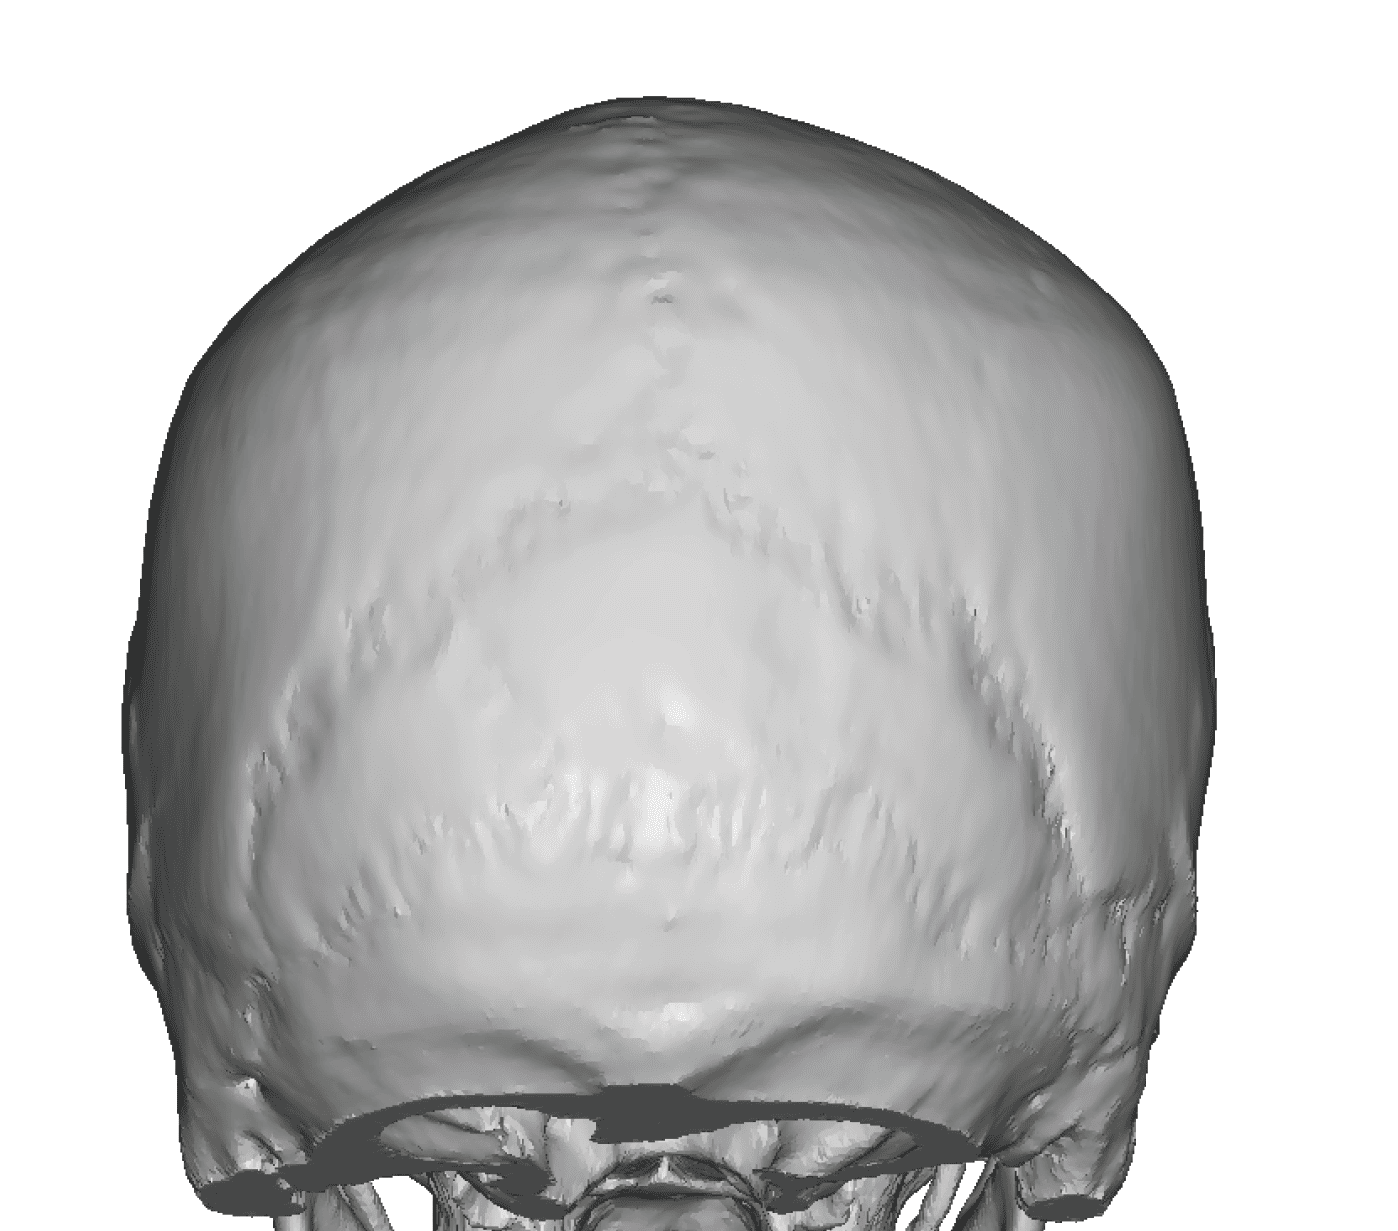

Patient 100

Desire for reshaping of an asymmetric flat back of the head in a shaved head male.

A combined back of the head reshaping procedure was done with a custom skull implant, sagittal ridge reduction and a right temporal muscle reduction.

Desire for reshaping of an asymmetric flat back of the head in a shaved head male.

A combined back of the head reshaping procedure was done with a custom skull implant, sagittal ridge reduction and a right temporal muscle reduction.